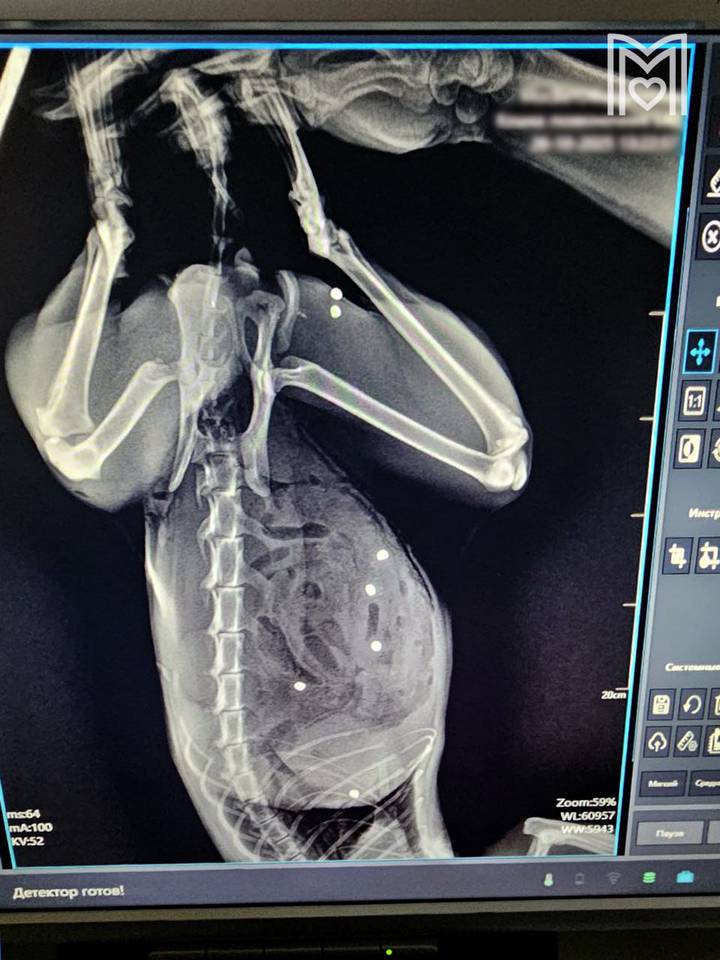

Расстрелянного из ружья кота с более чем 20 ранениями спасли московские ветеринары

Фото: Мосветобъединение

Зеленоградские ветеринары спасли пятилетнего кота по кличке Тимофей с 20 пулевыми ранениями. Он пострадал во время прогулки в частном секторе. Об этом в пятницу, 28 ноября, сообщили в пресс-службе «Мосветобъединения».

Пушистого пациента осмотрел хирург Евгений Цыбин, который выяснил, что у того пробит кишечник в 24-х местах и в двух местах — селезенка, также пули попали в грудную клетку и мышцы бедра. Доктор немедленно приступил к операции, которая заняла три часа. После Тимофей пошел на поправку, и сегодня его здоровье уже вне опасности.

— Под конец операции и кот, и я выглядели одинаково... Не скрою, горжусь собой на 100 процентов, но еще больше котом! Несмотря нa все усилия живодеров, котик жив! — передает слова ветврача официальный Telegram-канал учреждения.

Расстрелянного из ружья кота с более чем 20 ранениями спасли московские ветеринары  Фото: Мосветобъединение